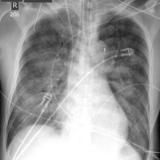

APE 2

Date: 11/05/2005

Views: 2684